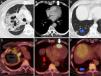

We report the case of a 64-year-old man with a clinical picture of anorexia, asthenia and weight loss, who developed obstructive pneumonia after admission to our hospital. A computed tomography was performed, showing a pulmonary mass with a large central necrotic area in the right upper lobe, a 20mm hypodense cardiac lesion in the apex of the right ventricle consistent with metastasis, and an image suggestive of subpleural pulmonary infarction in the right lower lobe (Fig. 1A–C).

(A–C) Chest CT after administration of intravenous iodized contrast, lung (A and C) and mediastinum (B) windows. (D–F) PET/CT after administration of 18F-FDG. Mass in right upper lobe with large areas of necrosis and cavitation (A) with increased peripheral glucose metabolism (D). Lesion in the apex of the right ventricle (B and E, arrow) suggestive of cardiac metastasis. Image of peripheral base nodule containing air space in the right lower lobe (C, arrow) suggestive of pulmonary infarction. This lesion was metabolic on the PET/CT (F, arrow), and a hypermetabolic arterial embolism was observed in the feeding artery of that segment (E, gray arrow) consistent with tumor embolism.

Fiberoptic bronchoscopy was performed, and a specimen of the pulmonary mass was obtained and identified as non-small cell lung cancer. To complete the study, an 18F-FDG PET/CT was performed, revealing hypermetabolism of the pulmonary mass, the cardiac lesion, and the area of pulmonary infarction, and in a pulmonary artery of the right lower lobe (Fig. 1D–F). Uptake by the pulmonary infarction suggested that it was caused by tumor embolism.